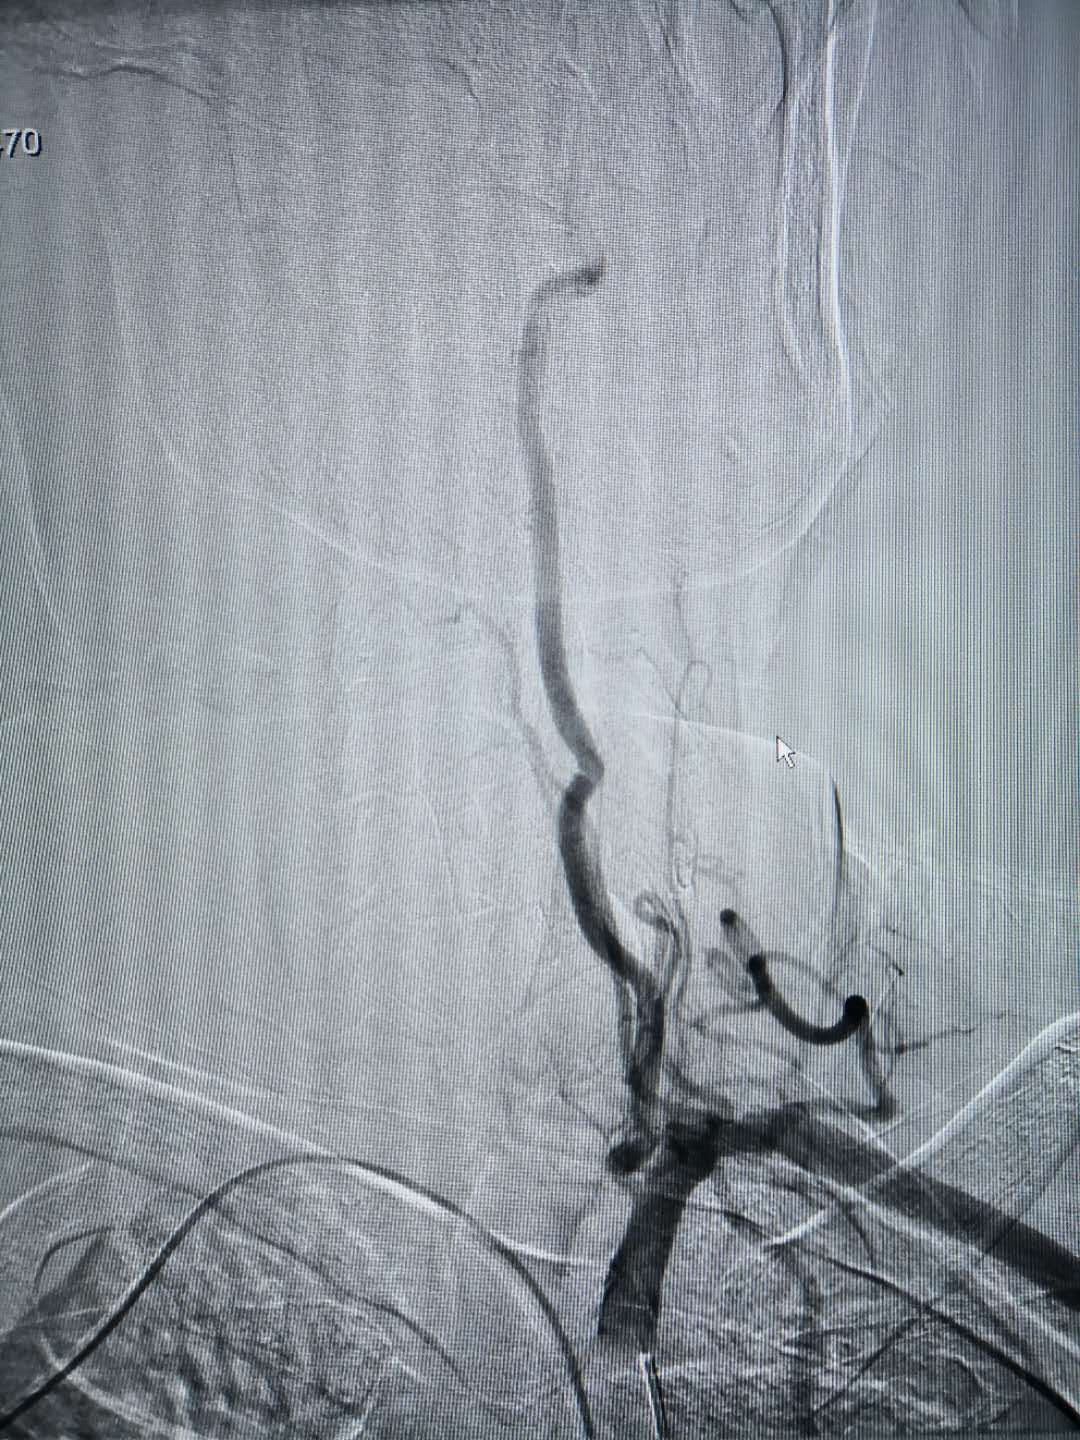

置入造影导管后相关血管造影图,所选择的血管清晰可见

经动脉鞘管置入造影导管行造影术 经桡动脉穿刺置入动脉鞘管 术后:使用小巧的桡动脉压迫器压迫固定桡动脉